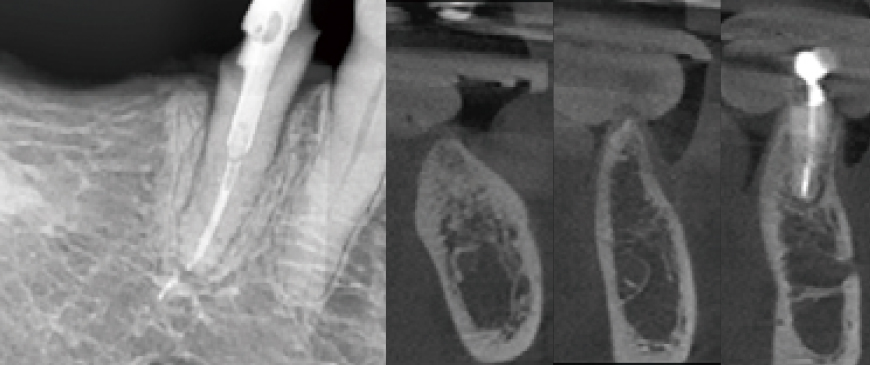

Postoperative panoramic and CBCT radiographs revealed minimal buccal bone thickness around the first molar implant, with the machined cuff of the BD Cuff occupying this space (indicated between the two arrows).

Fig 9

After approximately eight weeks, scanning was performed for impression-taking, followed by the placement of a customized abutment based on the BOPT (Biologically Oriented Preparation Technique) concept and a PMMA provisional bridge.